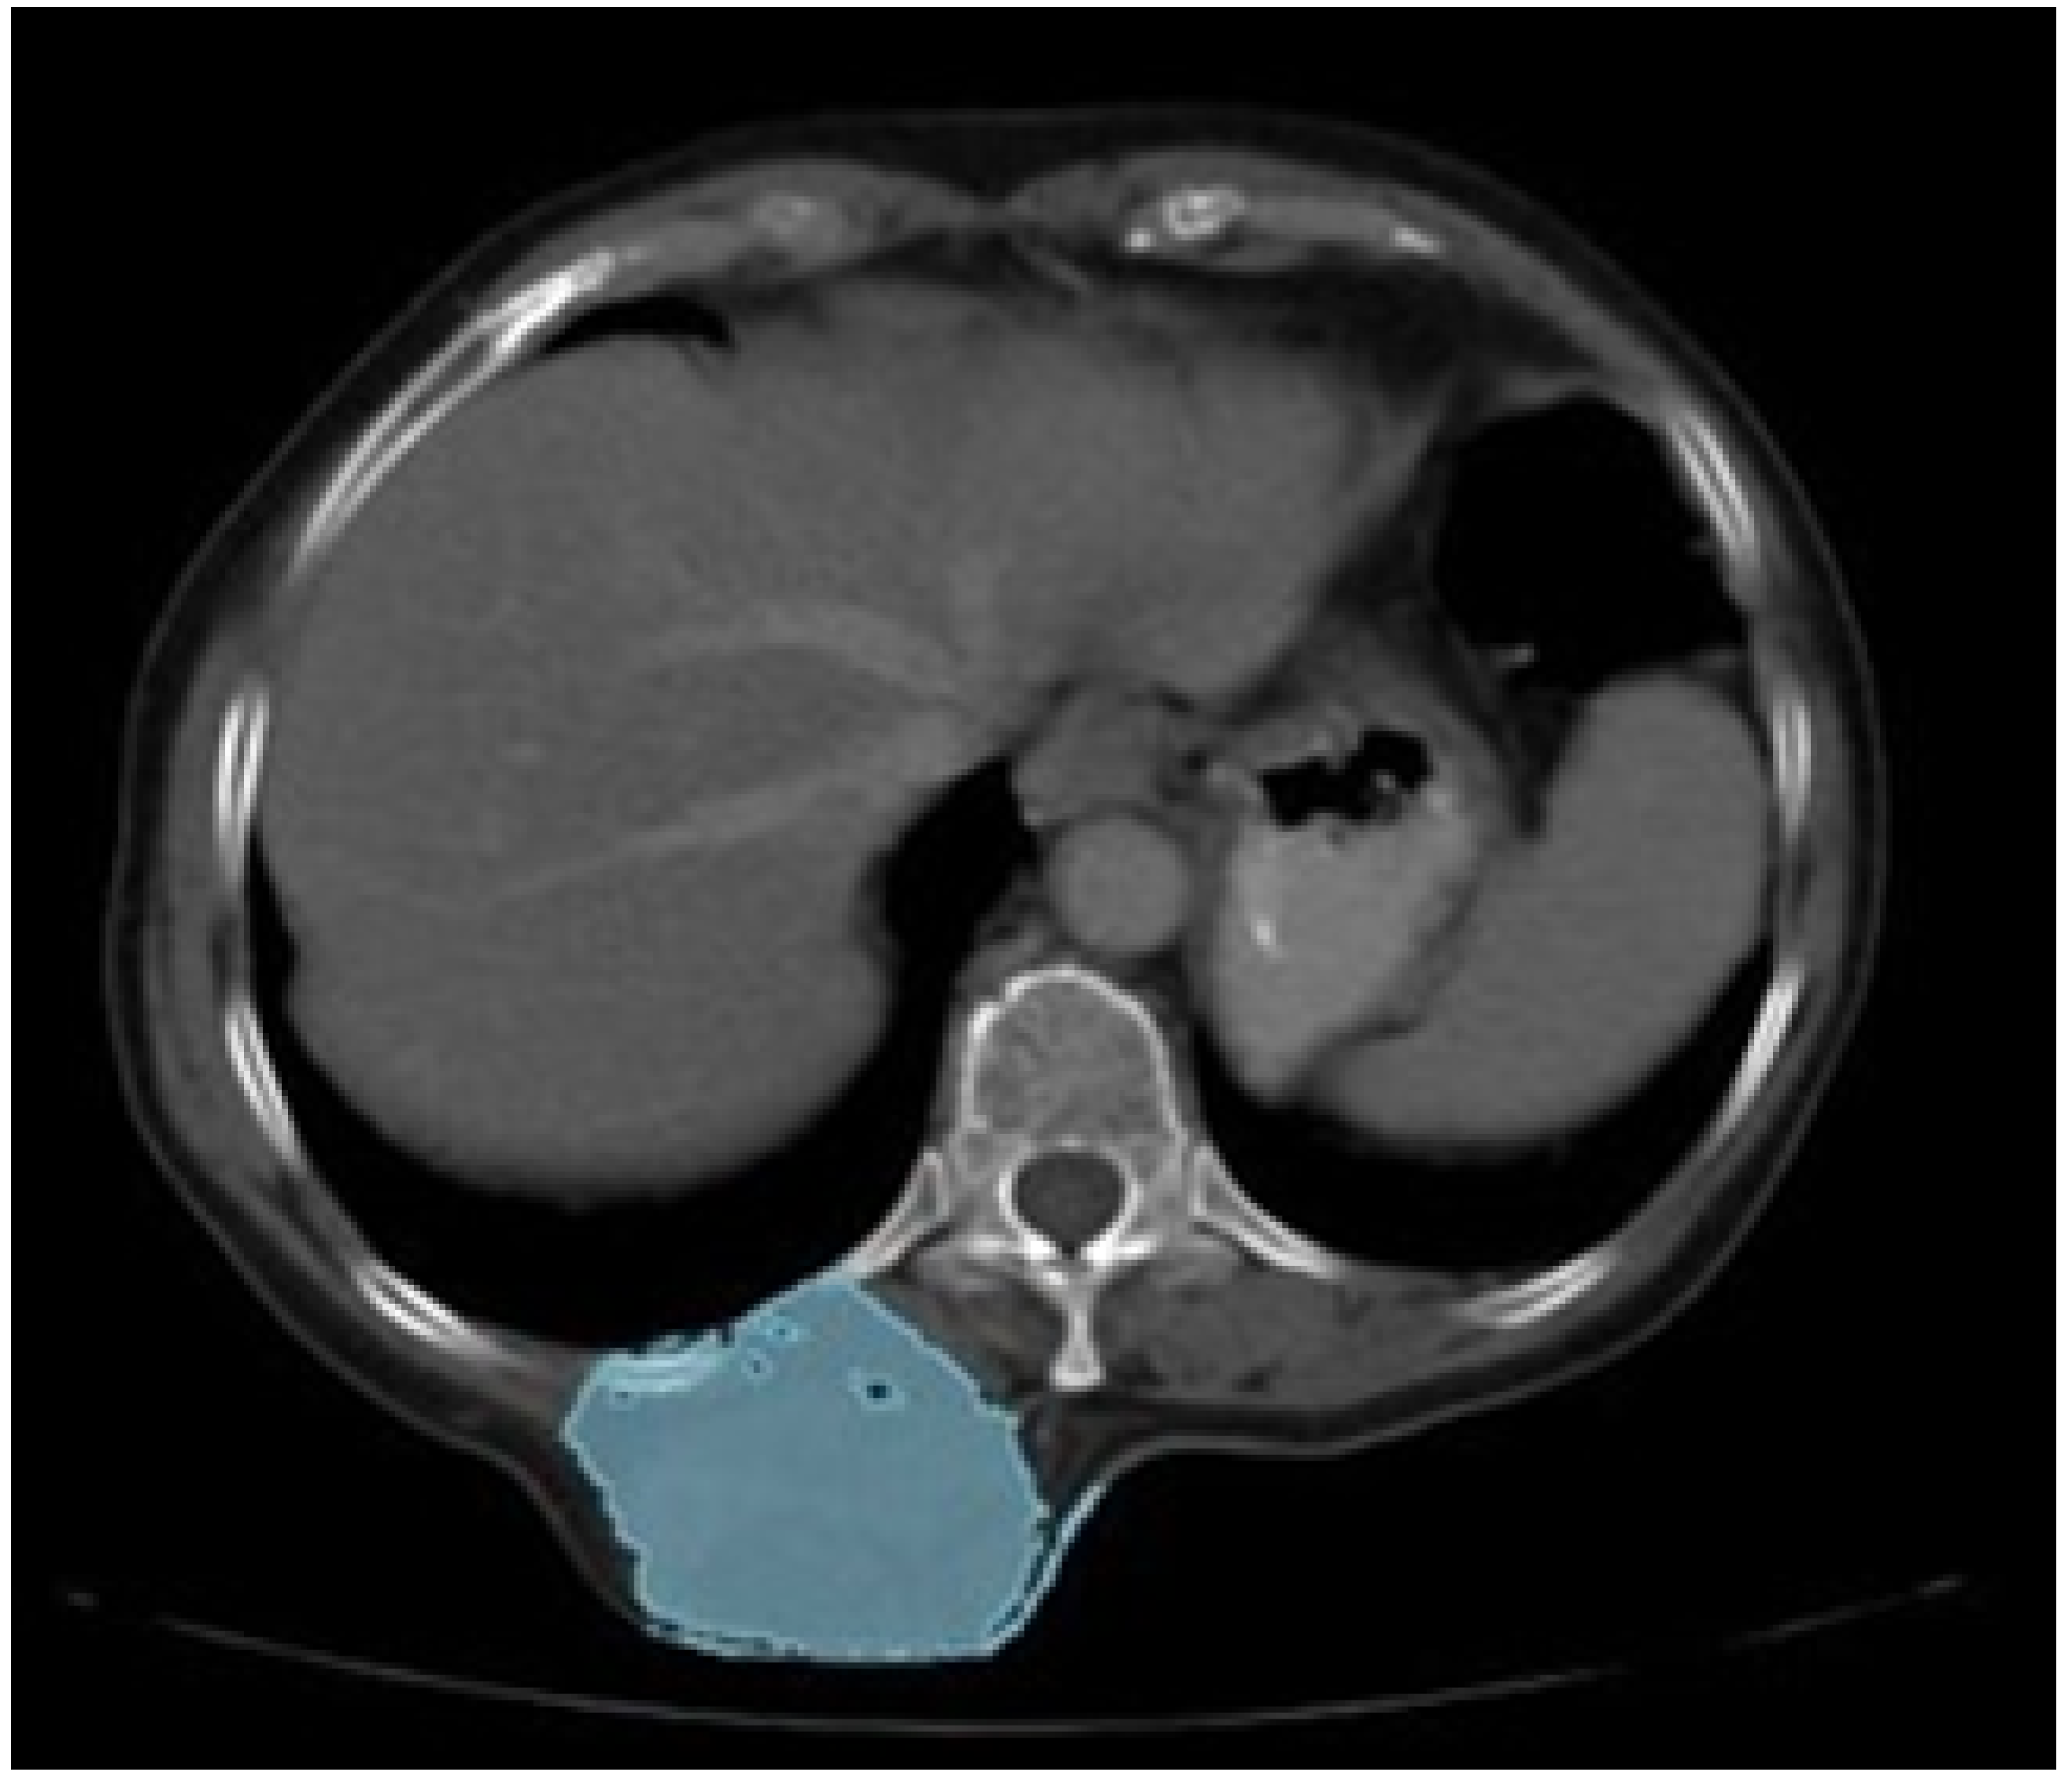

A 55-year-old female patient was diagnosed with osteosarcoma of the right sternoclavicular joint. This condition resulted in pain in the joint and limited the mobility of the right upper extremity (see Figure 24).

The surgical excision of the tumour was performed through simulated surgery. The manufacturing process involved the creation of a cutting guide to facilitate the procedure and fabrication of a 3D patient-specific prosthesis. In the context of the phase of simulated surgery and the design of medical devices, a customised cutting guide was obtained from the study of tomographic images. To this end, the digital model of the anatomical surface with osteosarcoma was generated using image segmentation algorithms, the bone structure was identified, and a 5 cm notch was made in the direction of the acromial extremity to facilitate cutting (Figure 25).

Figure 24. Presurgical tomography.